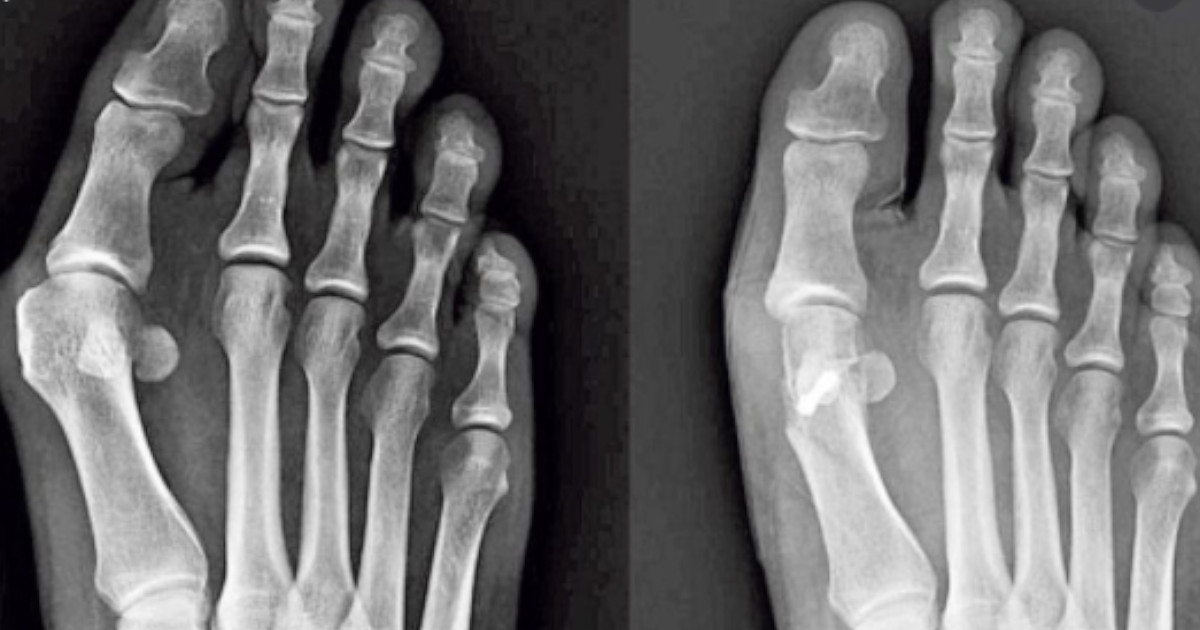

Haluks to kościsty guzek, który tworzy się na stawie u podstawy dużego palca. Występuje, gdy niektóre kości w przedniej części stopy przesuwają się z miejsca. Powoduje to, że czubek dużego palca u nogi zostaje pociągnięty w kierunku mniejszych palców i zmusza staw u podstawy dużego palca do wystania.

Skóra nad guzem może być czerwona i obolała. Noszenie obcisłych, wąskich butów może powodować haluksy lub je pogarszać. Haluksy mogą również rozwinąć się w wyniku kształtu stopy, deformacji stopy lub stanu chorobowego, takiego jak zapalenie stawów. Haluksy tworzą się w stawie.